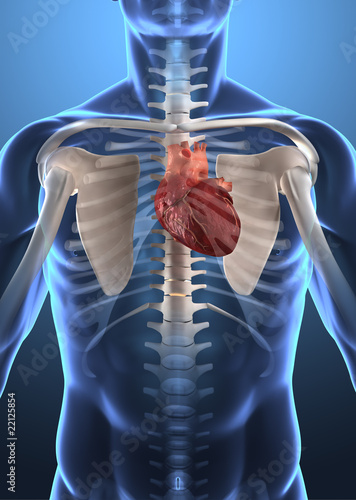

2) Stres ze sníženého přísunu kyslíku.

Jeden z důsledků je zvýšené napětí mezižeberních svalů, to v důsledku znamená, že svaly jsou přetížené a dochází ke stažení celého hrudního koše. Tím má tělo menší šanci plně se nadechnout. A podstatně se tak změlčuje naše běžné dýchání. Co s tím? Vědomá dechová cvičení se zaměřením na cílené dýchání do hrudního koše, aktivaci bránice. Dýchání „říkám tomu dýchat 3D. Níže najdete tip – cvik na uvolnění hrudníku.

3) Zpomalení trávení.

Celkově menší prokrvení hrudníku, dutiny břišní vede i ke zpomalení trávení. Podstatně se mi zvýšil počet klientů, kteří se potýkají s menšími či většími problémy s trávením. A co s tím? Na začátku dýchejte. Vědomě dýchejte i do břicha. Pomohou vám i éterické oleje. Tipy pro uvolnění a lepší dýchání najdete níže. Jak upravit jídelníček a jak pomáhá vědomé stravování v dnešní době si rozebereme v dalším článku.

I. TIP: Jak uvolnit hrudník?

Tady máte jeden cvik, který pomůže uvolnit hrudník, lopatky, mobilizovat ramena a také krásně aktivovat lymfatické uzliny v dutině hrudní a břišní!